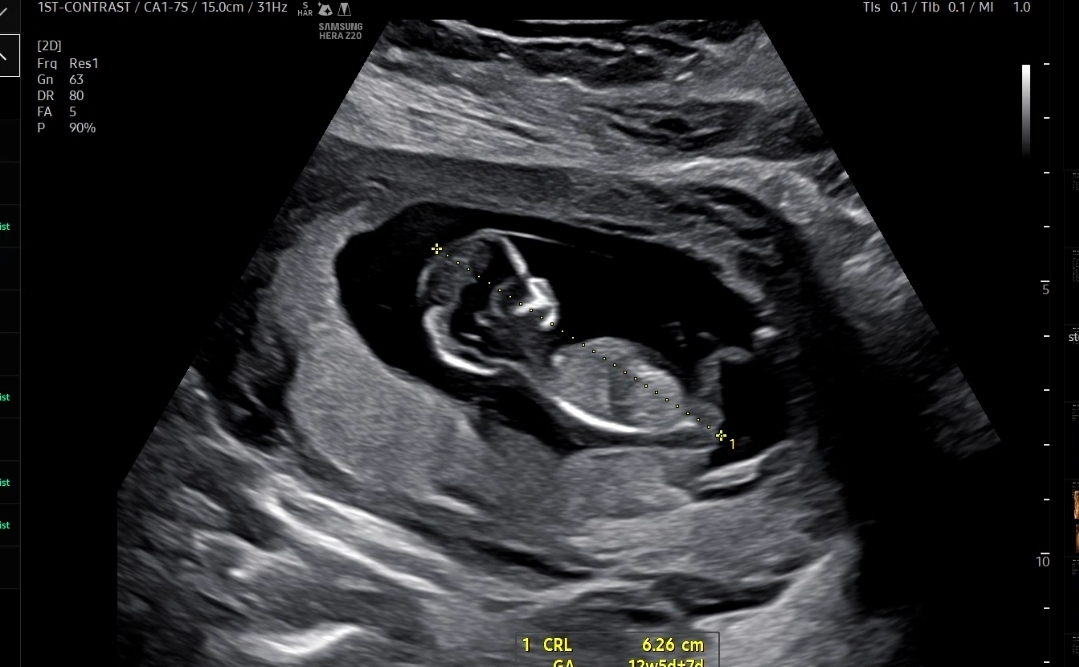

임신 12주 2일 1차 기형아 검사

기형아 검사는 NT(목투명대)를 보는 초음파와 피검사로 시행했고

먼저 예약된 시간된 시간에 맞춰 NT초음파를 보는 초음파실로 갔다

우선 아기크기와 심장소리를 확인했는데 아기크기도 6.26cm, 심장소리도 171bpm으로 잘 뛰고 있었다

마지막으로 확인한 콧대길이, 소뇌?길이, 목투명대 길이를 쟀다

처음에 계속 뒤돌아 있어서 기침하고 했는데 약 10분간 애쓰다가 겨우 보여준 콧대

코뼈길이는 0.26cm, 목투명대는 1.31mm 로 둘다 정상범위!

만약에 코뼈가 낮거나 목투명대가 3mm이상이면 다운증후군 위험이 있다고 했다